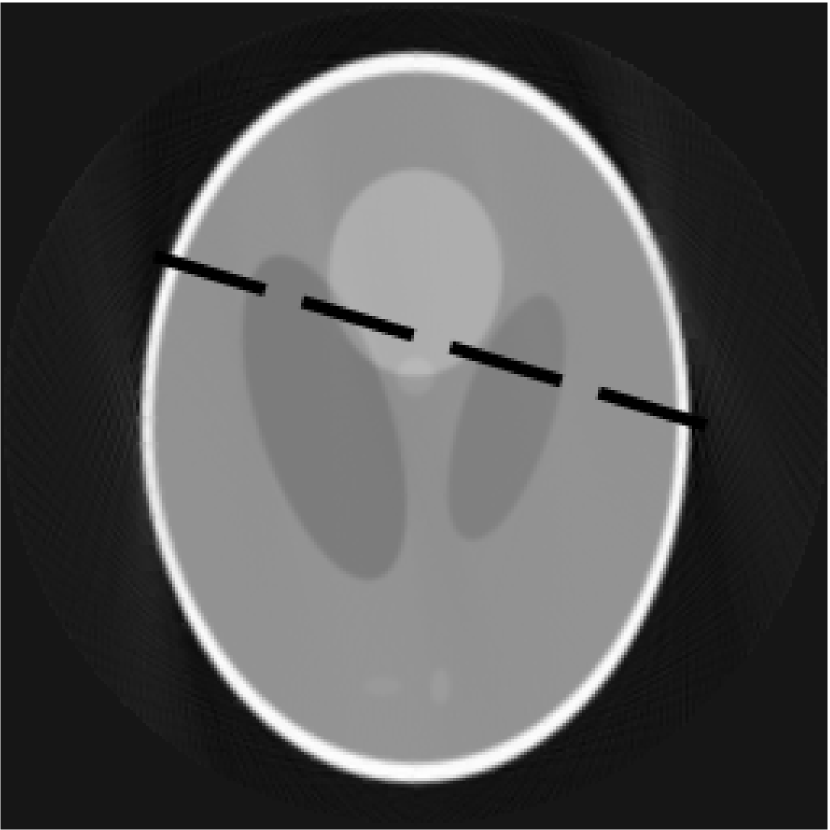

Figure 7: Slices reconstructed by the FDK(7a) and FDK-OD(7b), dashed line corresponds to profile below

Tests with real data have also been performed. Due to a presence of noise in real data, it can be observed in profiles. Obtained slices are shown in the figures 7a and 7b. The comparison of the profiles (figureΒ 8) reveals that the algorithm FDK-OD produces a smoother profile, while preserving sharp borders.